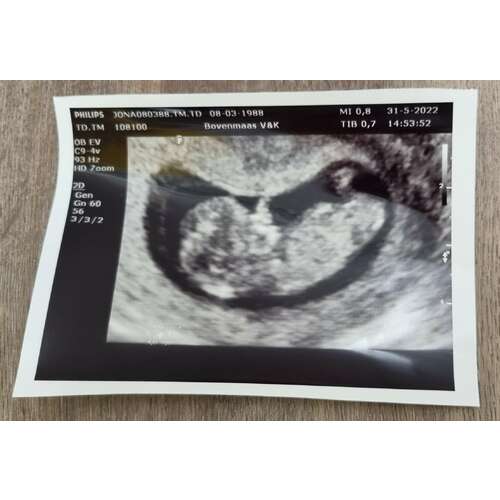

Uitgerekend op 31 december. Vandaag een prachtige echo gehad en mooi kloppend hartje gehoord

Vandaag termijn echo gehad, van 24-12 naar 22-12 gezet. Maar nr 1 was 3 dag ...